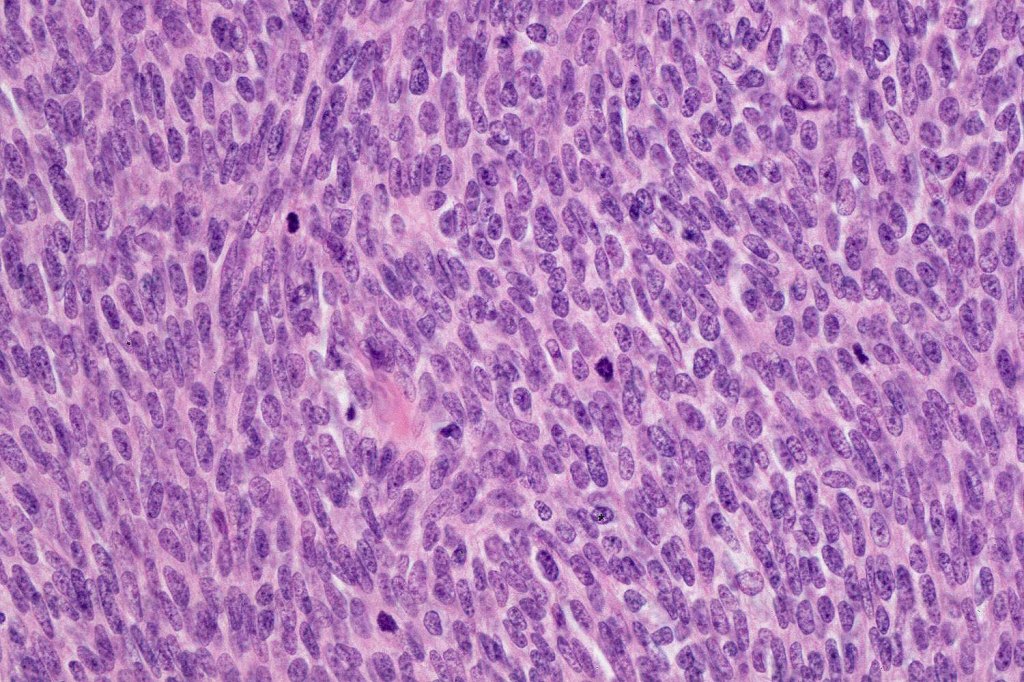

Histological features

•Well differentiated lobular growth pattern though to a poorly differentiated tumor often showing a diffuse, infiltrating border which may extend into the subcutaneous fat

•Tumors are composed of an admixture of darkly staining basaloid cells with hyperchromatic or vesicular nuclei and more obvious sebaceous cells with eosinophilic, bubbly, multivacuolated cytoplasm frequently indenting the nucleus (scalloped)

•Often mitoses are numerous and abnormal forms evident

•May be graded into well, moderate & poorly differentiated categories. I am not sure that this has any great value

Sebaceous carcinoma from a patient with Muir-Torre syndrome kindly shared by Dr. Antonina Kalmykova.